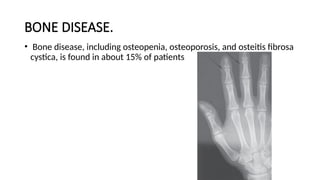

BONE DISEASE.

• Bone disease, including osteopenia, osteoporosis, and osteitis fibrosa

cystica, is found in about 15% of patients